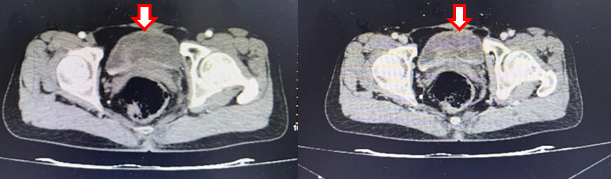

- Cắt lớp vi tính ổ bụng:

Hình 8: Cắt lớp vi tính ổ bụng (06/03/24): Không thấy hình ảnh u cục, tổn thương thứ phát tại bàng quang (mũi tên)

Hình 9: Cắt lớp vi tính ổ bụng (06/03/24): Hình ảnh u máu gan phải, khối lớn nhất kich thước 36x52mm (mũi tên)